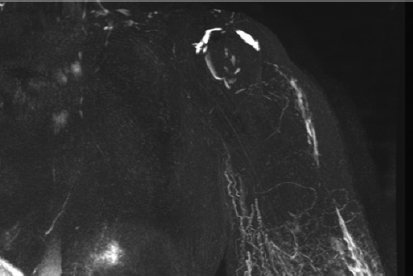

Major progress has been achieved in the radiologic diagnosis of patients with lymphedema. MR lymphangiography with T2-weighted imaging allows visualization of the anatomy of the lymphatic system with greater sensitivity than lymphoscintigraphy and potentially without the need for any injection, 1 , 2 although the use of gadolinium with venous suppression probably yields more consistent images. The ideal treatment of the affected limb should restore both function and the cosmetic appearance. Physical therapy is the most commonly performed treatment for chronic lymphedema, and many consider it the only treatment for long-term management. Certainly, it helps to control to some extent the evolution of the disease, but it is not a curative therapy.

MR lymphangiography helps identify the type of edema and is critical to deciding the best treatment option.

Identifying the problem is very important because it guides the surgeon on the optimal placement of the lymph nodes and which lymphatic pathways must be targeted during physical therapy. MR lymphangiography is the best investigation tool to evaluate the problem. The flap can be sometimes enlarged to reconstruct the breast defect and fibrotic area in the axillary or inguinal region.

Congenital lymphedema can present in various forms. Lymphoscintigraphy yields poor results and in our practice has been completely replaced by MR lymphangiography. However, this form of imaging is relatively new and is performed in only a few centers. The syndromes, hypoplastic or hyperplastic forms, and the level of the malformations are evaluated. Some individuals can present simultaneously, with both hypoplastic and hyperplastic forms in different parts of the body. VLNT is indicated in patients with hypoplasia, because lymphangiogenic proteins are contained in the transplanted nodes, and they simultaneously act as sump pumps to transfer some of the lymphatic fluid into the venous circulation. 8

Physical therapy was complementary to the surgical treatment. Compressive bandages were applied, and manual drainage was performed for the first 3 postoperative months and progressively reduced thereafter. Patients were evaluated by perimetry, volumetry, and quality of life, and preoperative and postoperative photographs were taken after 6 and 12 months and 2 and 5 years. Between 1992 and 2011, lymphoscintigraphy was performed preoperatively and 1 and 5 years postoperatively. However, the correlation with the clinical results was not always appropriate. Since 2011, MR lymphangiography has yielded superior information and excellent images of the lymphatic system.